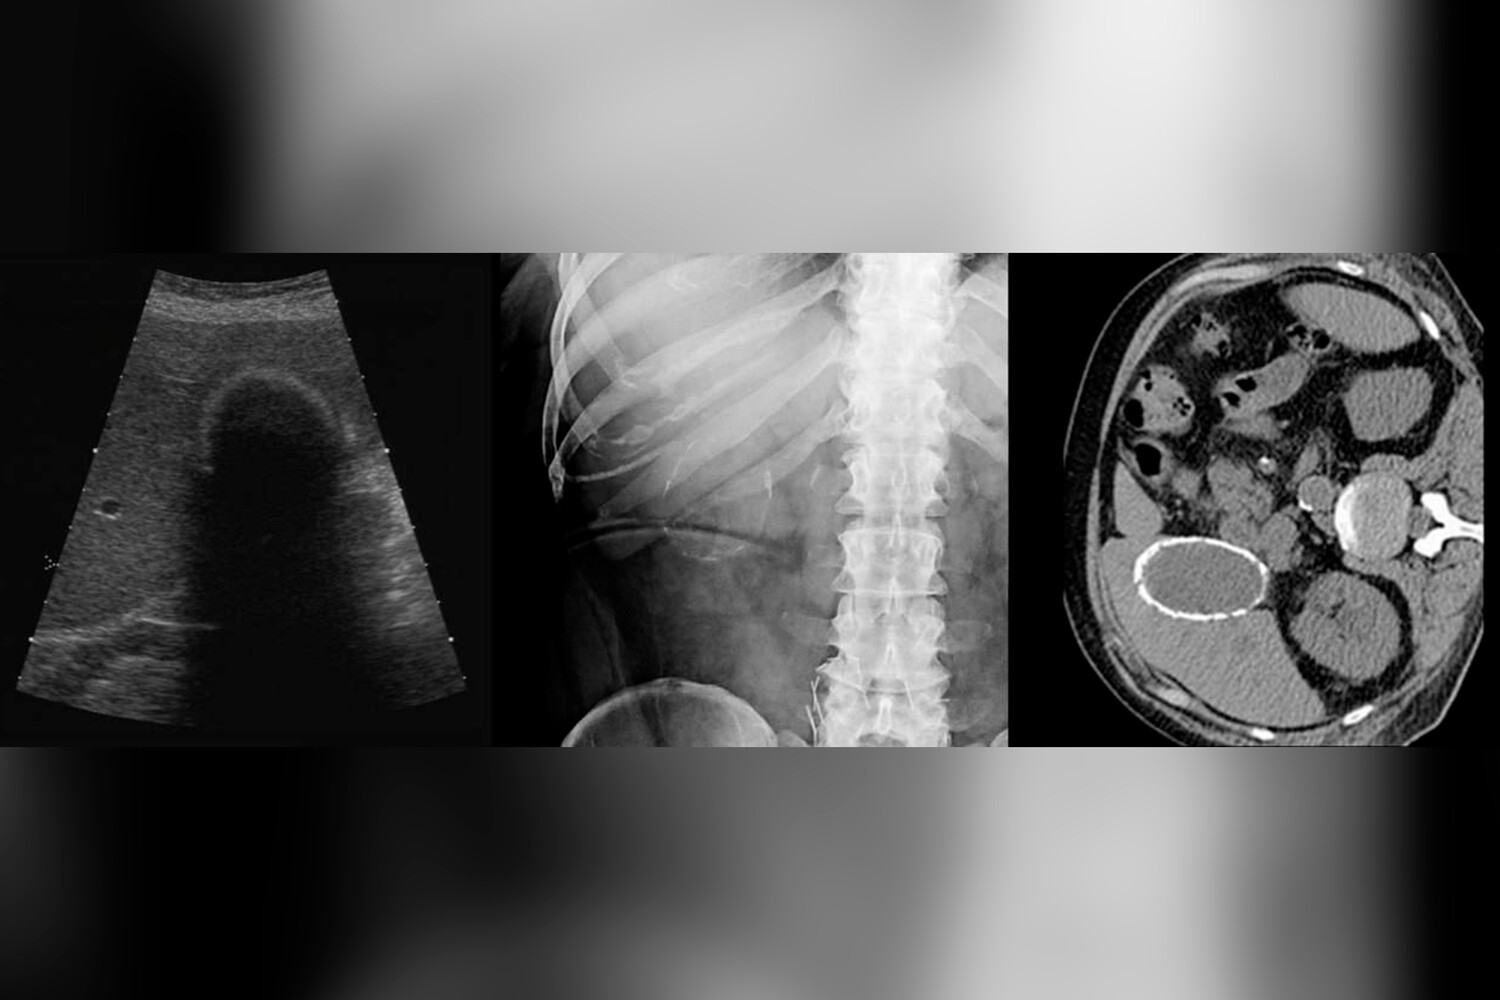

Врачи городской больницы Реутова прооперировали местную жительницу с редкой патологией — «фарфоровым» желчным пузырем. Об этом сообщили в пресс-службе минздрава Московской области.

Женщина обратилась с жалобами на тяжесть в правом подреберье. Ей диагностировали редкую разновидность калькулезного холецистита, когда стенки пузыря покрываются слоем кальция, делая орган твердым.

«Сам пузырь настолько затвердел, что его было почти невозможно разрезать скальпелем», — поделились медики.